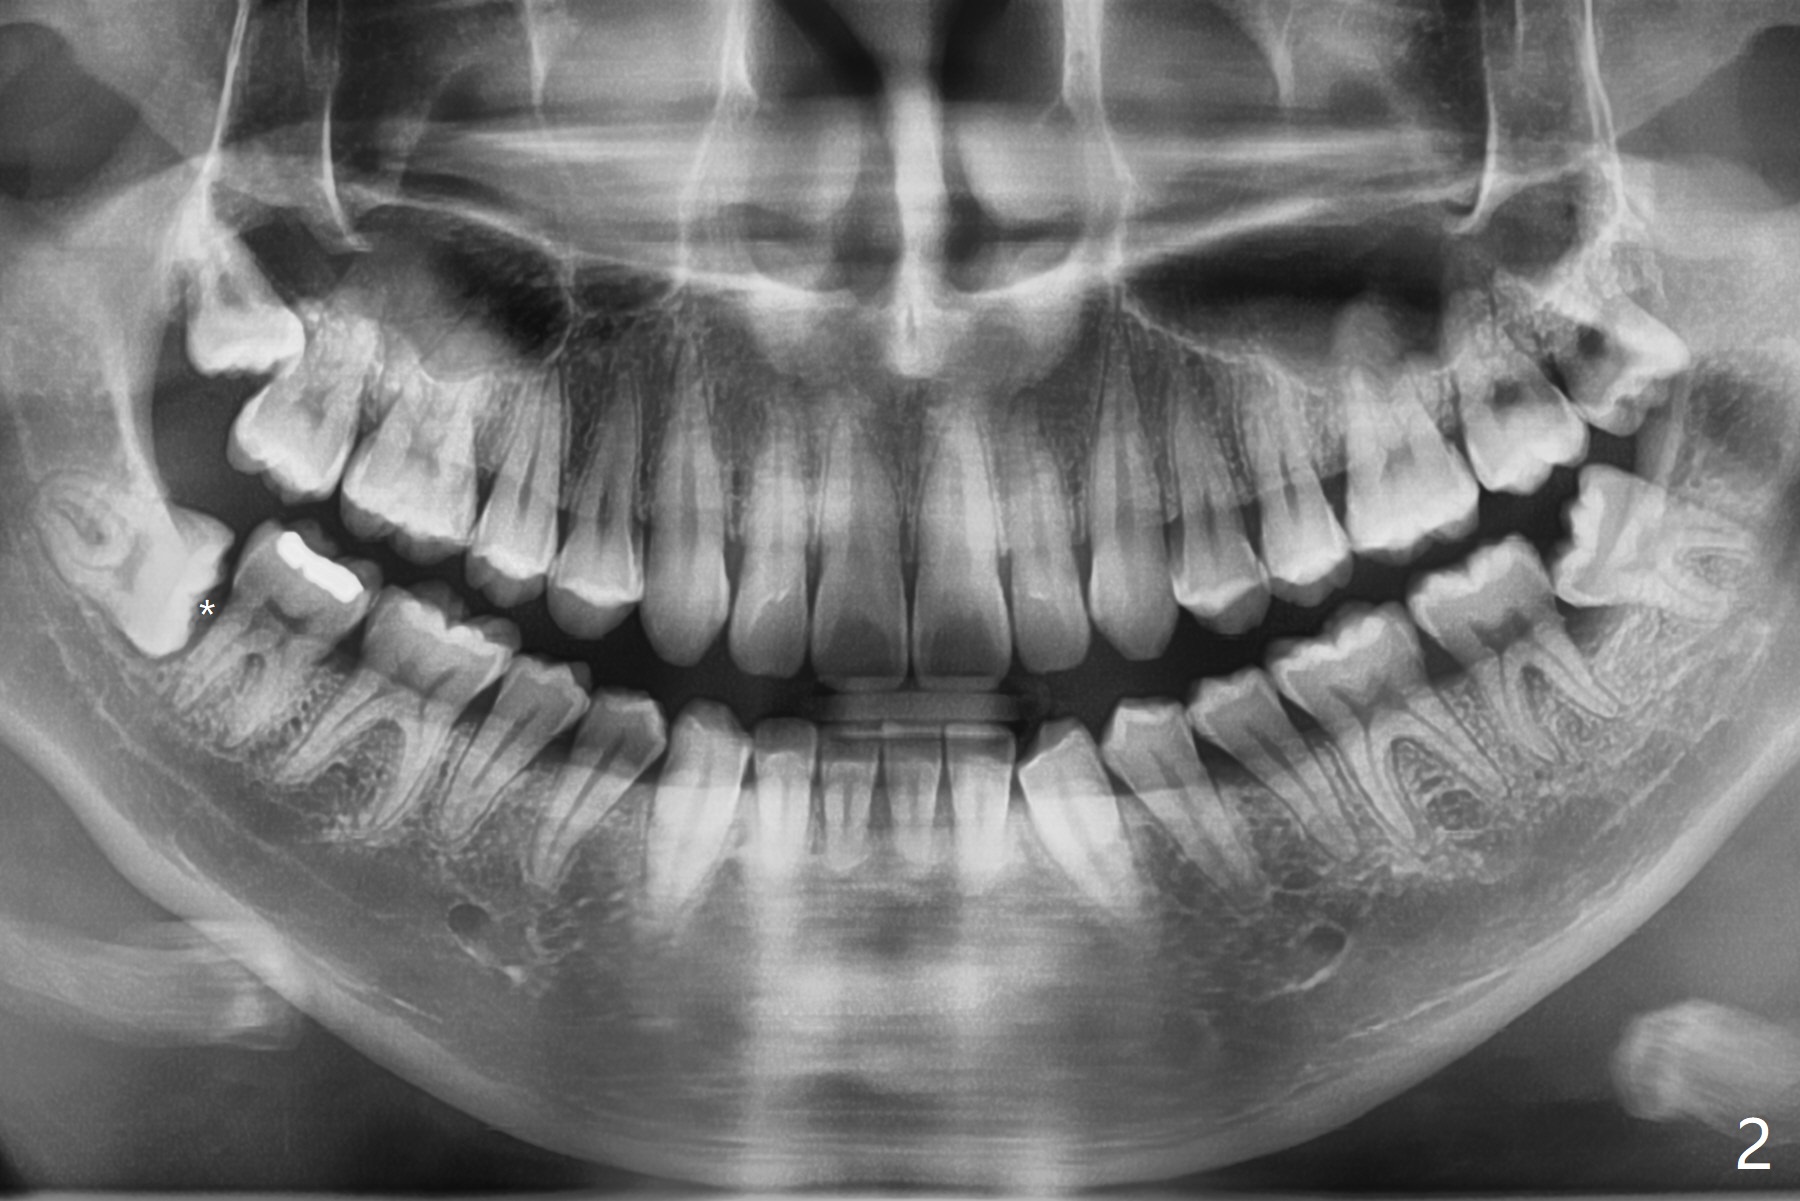

A 22-year-old man with poor oral hygiene requests extraction of the lower right 3rd molar. The buccal gingiva of the 2nd molar is erythematous and edematous (Fig.1 *). There is tenderness between #31 and 32 with severe bone loss (Fig.2 *). After extraction and debridement (Fig.3), Osteogen plug is inserted into radicular portion of the socket (Fig.4 white outline), while allograft is placed coronally (Fig.5, 7), covered by Collagen plug (Fig.6) before suturing. The bone fills the whole socket 1 year postop (Fig.8); there is no root surface exposure at #31. The bone fills the whole socket of #32 one year postop (Fig.8); there is no root surface exposure at #31.